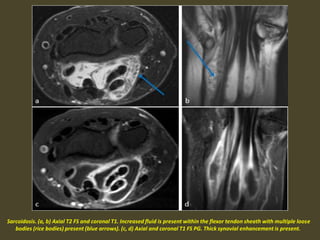

Sarcoidosis. (a, b) Axial T2 FS and coronal T1. Increased fluid is present within the flexor tendon sheath with multiple loose

bodies (rice bodies) present (blue arrows). (c, d) Axial and coronal T1 FS PG. Thick synovial enhancement is present.